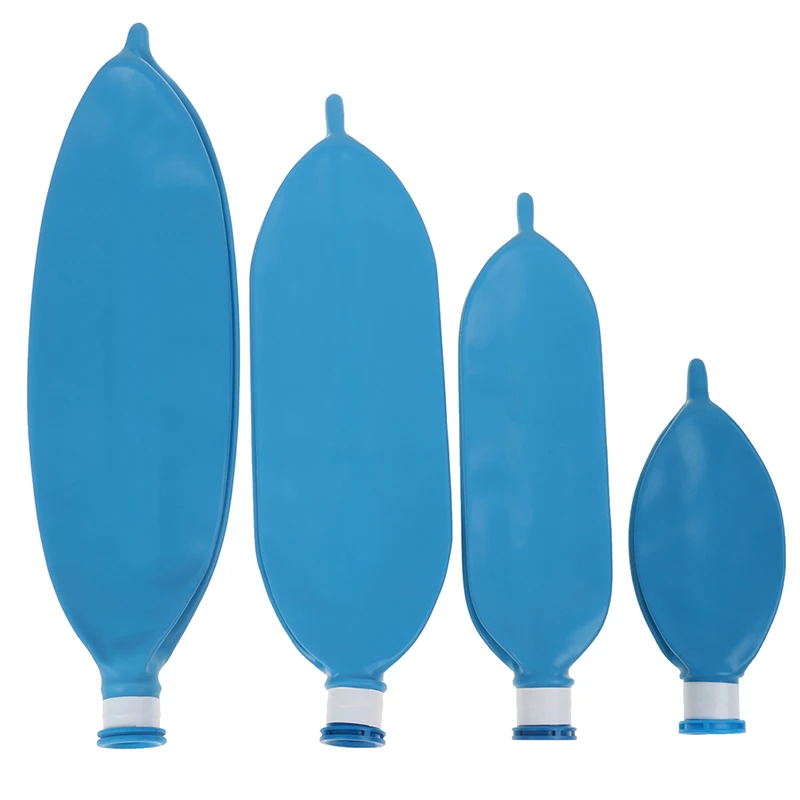

Латексный одноразовый дыхательный аппарат для анестезии объемом л, 1 л, 2 л, 3 л

Описание:Материал: латексРазмер: 0.5л 1Л 2л 3лЦвет: синий